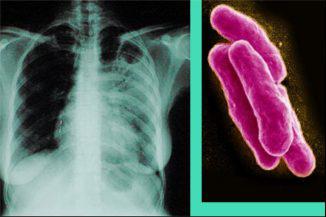

Tuberkulózis - egy veszélyes fertőző betegség. A betegség nem csak egy erős hatása van a szervezetre, ami súlyos állapotban van, de halálhoz is vezethet az érintett személy betegség. És a betegség okozza egy bizonyos típusú kórokozó (Mycobacterium), van egy nagy lehetőséget, hogy elterjedt a fertőzés emberek között körülvevő beteg tuberkulózisban.

Tuberkulózis befolyásolja a különböző szervek és rendszerek. A modern orvostudomány 74 típusú mikroorganizmusok okozó patológiás folyamatok, amelyek elpusztítják ideg vagy a nyirokrendszerbe, a nemi szervek, a belek, a vese és a húgyutak és néha az egész testet. Ugyanakkor a leggyakoribb típus a tüdőbetegség tuberkulózis. Ez a forma a betegség fordul elő 90% -ában.